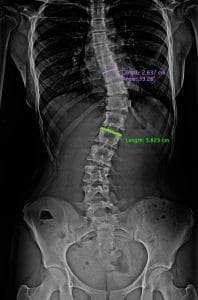

Un espinograma es un estudio radiográfico especial que permite obtener una visión panorámica completa de toda la columna vertebral, desde la base del cráneo hasta la pelvis, en una sola imagen. A diferencia de las radiografías convencionales, que suelen enfocarse solo en un segmento (como la columna cervical o dorsal), el espinograma captura la relación entre todas las piezas del rompecabezas óseo, permitiendo evaluar cómo se compensan unas con otras.

La principal función de este estudio es evaluar la alineación vertebral. En una visión de frente, la columna debe presentarse perfectamente recta desde arriba hacia abajo. Los médicos suelen compararlo con la «plomada de un albañil»: si trazamos una línea vertical desde el centro del cuello, esta debe caer exactamente en medio de la pelvis. Cualquier desviación lateral de esta línea podría indicar la presencia de una escoliosis.

El espinograma es pedido frecuentemente para pacientes con sospecha de escoliosis, especialmente en adolescentes durante su etapa de crecimiento. Al ser una placa única, permite medir el «ángulo de Cobb», que determina la gravedad de la curva lateral y ayuda a decidir si es necesario el uso de corsé o, en casos severos, una cirugía de corrección.

Actualmente se realizan espinogramas digitales que permiten de manera informática medir la alineación y los ángulos de las curvaturas de la columna tanto normales como patológicas.

Esta mediciones múltiples muestra con mayor exactitud los ángulos de Cobb.

Es el ángulo formado por líneas paralelas a los platillos superior e inferior de la curva estructural, mayor o primaria que está delimitada por las vértebras límite (transicionales) superior e inferior.